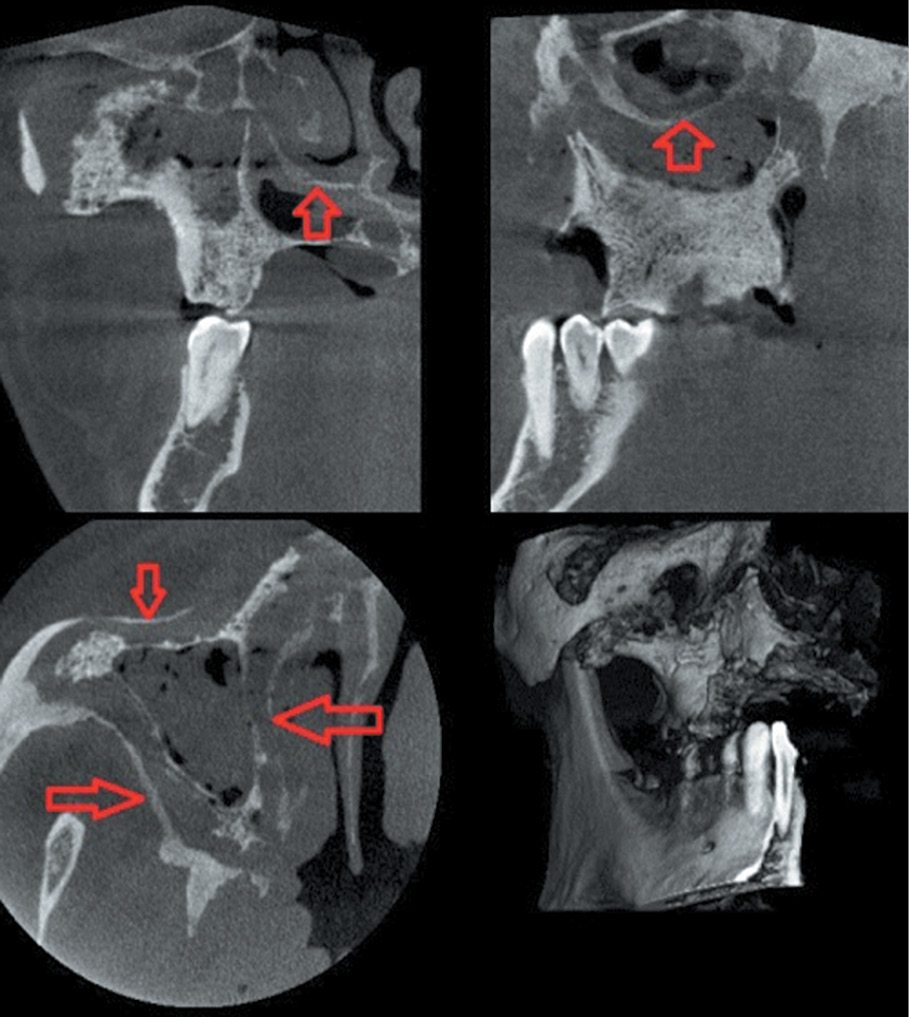

An upper jaw lesion with the formation of a demarcation line was observed in 8 participants (5 males and 3 females). Due to the anatomical features, upper jaw sequestration occurred earlier than in the lower jaw (on average, 13 ± 1 weeks). The timing depended on the extent of the lesion in the maxilla. The formation of the demarcation line increased up to 3 years in the case of total upper jaw damage that involve the adjacent areas of the zygomatic bone (Fig. 7).

Fig. 7. The sequestration in the maxilla with involvement of the zygomatic bone / Рис. 7. Секвестр в области верхней челюсти с вовлечением участка тела скуловой кости

The sequestration time was reduced to 6 weeks with a limited lesion of a part of the alveolar process within 2 or 3 teeth. A characteristic aspect of maxilla osteonecrosis was the involvement of the maxillary sinus in the purulent-inflammatory process. The development of maxillary sinusitis was noted in 5 out of 8 participants. Thus, sequestrectomy in this group of patients was combined with sinusotomy. It should be noted that in 2 patients with extensive damage to the upper jaw, a long sequestration process was combined with the formation of a bone “lintel” between the intact areas of the bone, the maxillary sinus, the nasal cavity walls, and the affected area of the maxilla (Fig. 8).

Fig. 8. The formation of bone “lintels” with extensive damage of the maxilla / Рис. 8. Формирование костных «перемычек» при обширном поражении верхней челюсти

In these cases, with the removal of sequesters, antrostomy or nasostomy was not formed. Therefore, these patients did not require extensive radical surgical interventions.